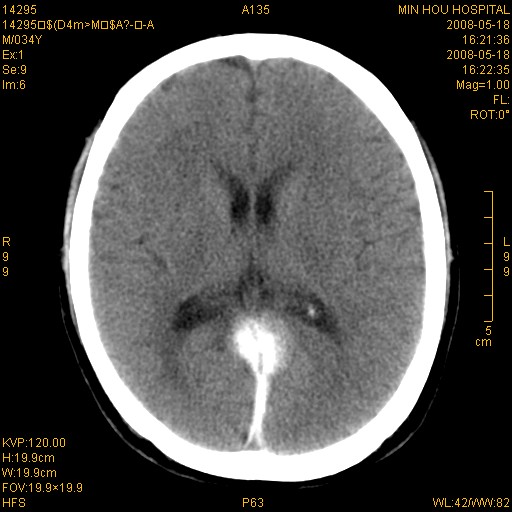

标题: CT13617:双顶叶白质水肿伴大脑镰小脑幕广泛钙化 [打印本页]

标题: CT13617:双顶叶白质水肿伴大脑镰小脑幕广泛钙化

多年前频发抽搐生活不能自理,行ct平扫,诊断为双顶叶占位。因贫未能进一步检查。

目前偶有抽搐,能从事油漆工作。原片未能获取。

双侧侧脑室后脚旁对称性低密度影,符合肾上腺白质营养不良(成人型)改变    小脑幕及大脑廉钙化  可考虑为生理性

支持:1、肾上腺白质营养不良.2、小脑幕、大脑镰广泛钙化。3、建议进一步检查。

硬脑膜钙化是主因,双侧顶叶白质密度减低是可能由于静脉路回流受阻所致。